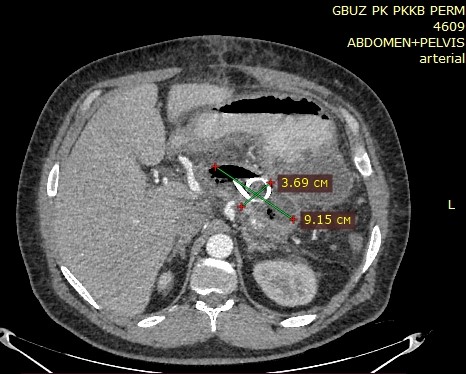

Через 2–3 суток пациенты отмечали уменьшение болевого синдрома, нормализацию температуры тела. Уровень амилазы оставался повышенным в 1,5–2 раза в 9 случаях. По результатам УЗИ и КТ киста через 2–3 дня после эндоскопического вмешательства полностью исчезла у 30,56 % пациентов, спалась на половину диаметра и более у 63,89 % и только у 5,56 % – уменьшилась незначительно (рис. 1–3).

Рис. 3. КТ органов брюшной полости с болюсным усилением, артериальная фаза. В просвете псевдокисты ПЖ находится дренаж типа double pig tail. Полость псевдокисты ПЖ уменьшилась в размерах в два раза